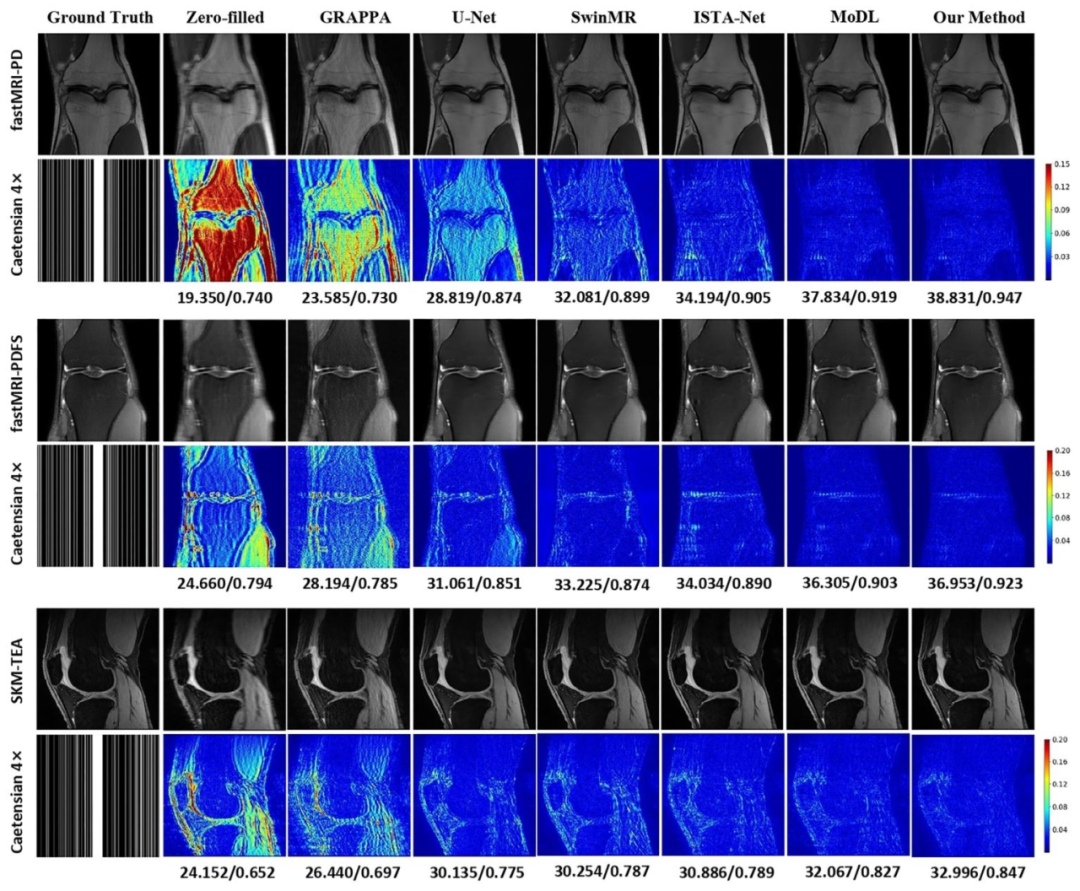

Fig. 3. Comparison of different methods under 4× acceleration on the fastMRI and SKM-TEA knee datasets. The reconstructed images and error maps are presentedwith the corresponding quantitative metrics in PSNR/SSIM.

图3 4倍加速下不同方法在fastMRI与SKM-TEA膝关节数据集上的性能对比 图中展示了各方法的重建图像与误差图,并标注了对应的峰值信噪比(PSNR)和结构相似性指数(SSIM)定量指标。